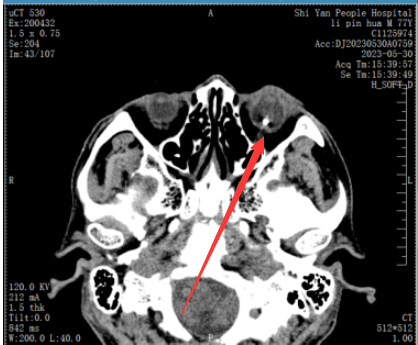

术前眼眶CT,可见金属异物正位于患者左眼视网膜上,情况十分凶险。

柯峰说,患者就诊时间虽与受伤时间相隔不长,但由于感染眼内组织结构已遭到严重破坏。目前手术治疗主要是为他保住眼球,但恢复视力的希望较渺茫。

为避免感染进一步加剧,柯峰当即为他进行了微创玻璃体切割+白内障摘除(外伤性白内障) +眼内异物取出+瞳孔成形+硅油填充+视网膜光凝手术。最终,在刘大爷左眼取出了一块约5mm*4mm的生锈铁器。